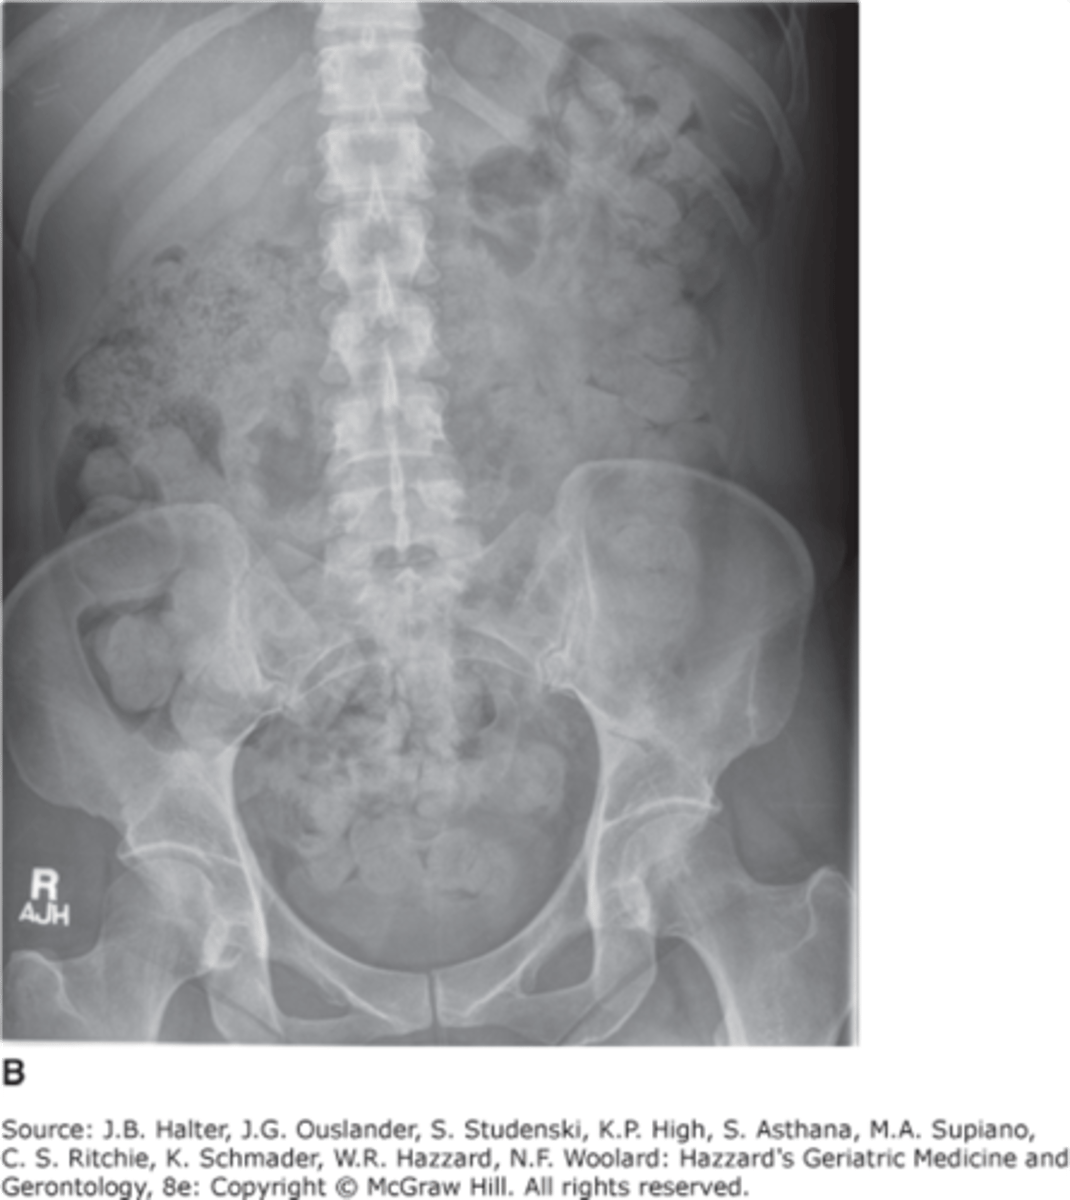

constipation

air in distal rectum, no bowel obstruction present

diverticulosis

outpouchings of colon, uncertain etiology, 90% pts asymptomatic, some pts have chronic constipation, abdominal pain, fluctuating bowel habits

diverticulosis CT

air filled outpouchings of colon that represent diverticula